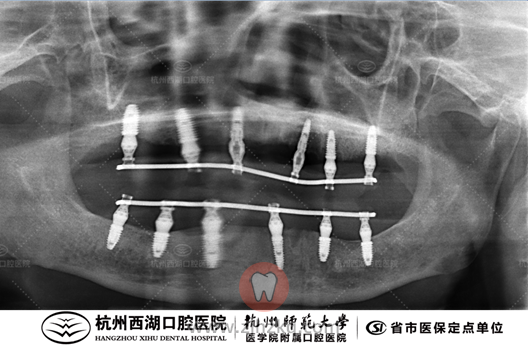

术后CBCT照如下